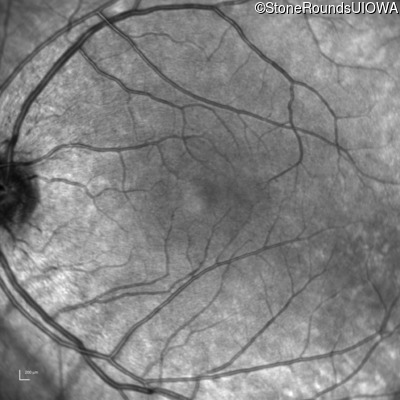

Infrared Fundus Photograph - Left - 20/20 -1

Exemplar